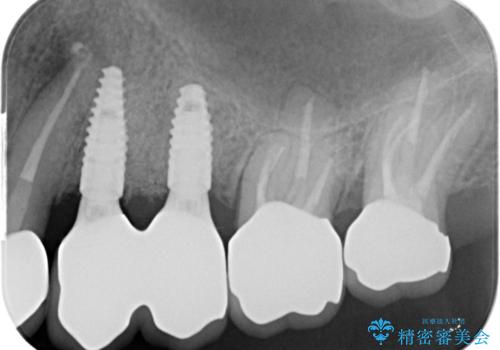

- 123.2万円(インプラント×2・チタンカスタムアバットメント×2・ジルコニアクラウン×4・仮歯×4)費用は治療当時の料金となります

ただ銀歯を外してセラミックにするだけではなく、長期的な観点に立ち長持ちするような環境を整備できるよう心がけ歯科治療をおこなっております。